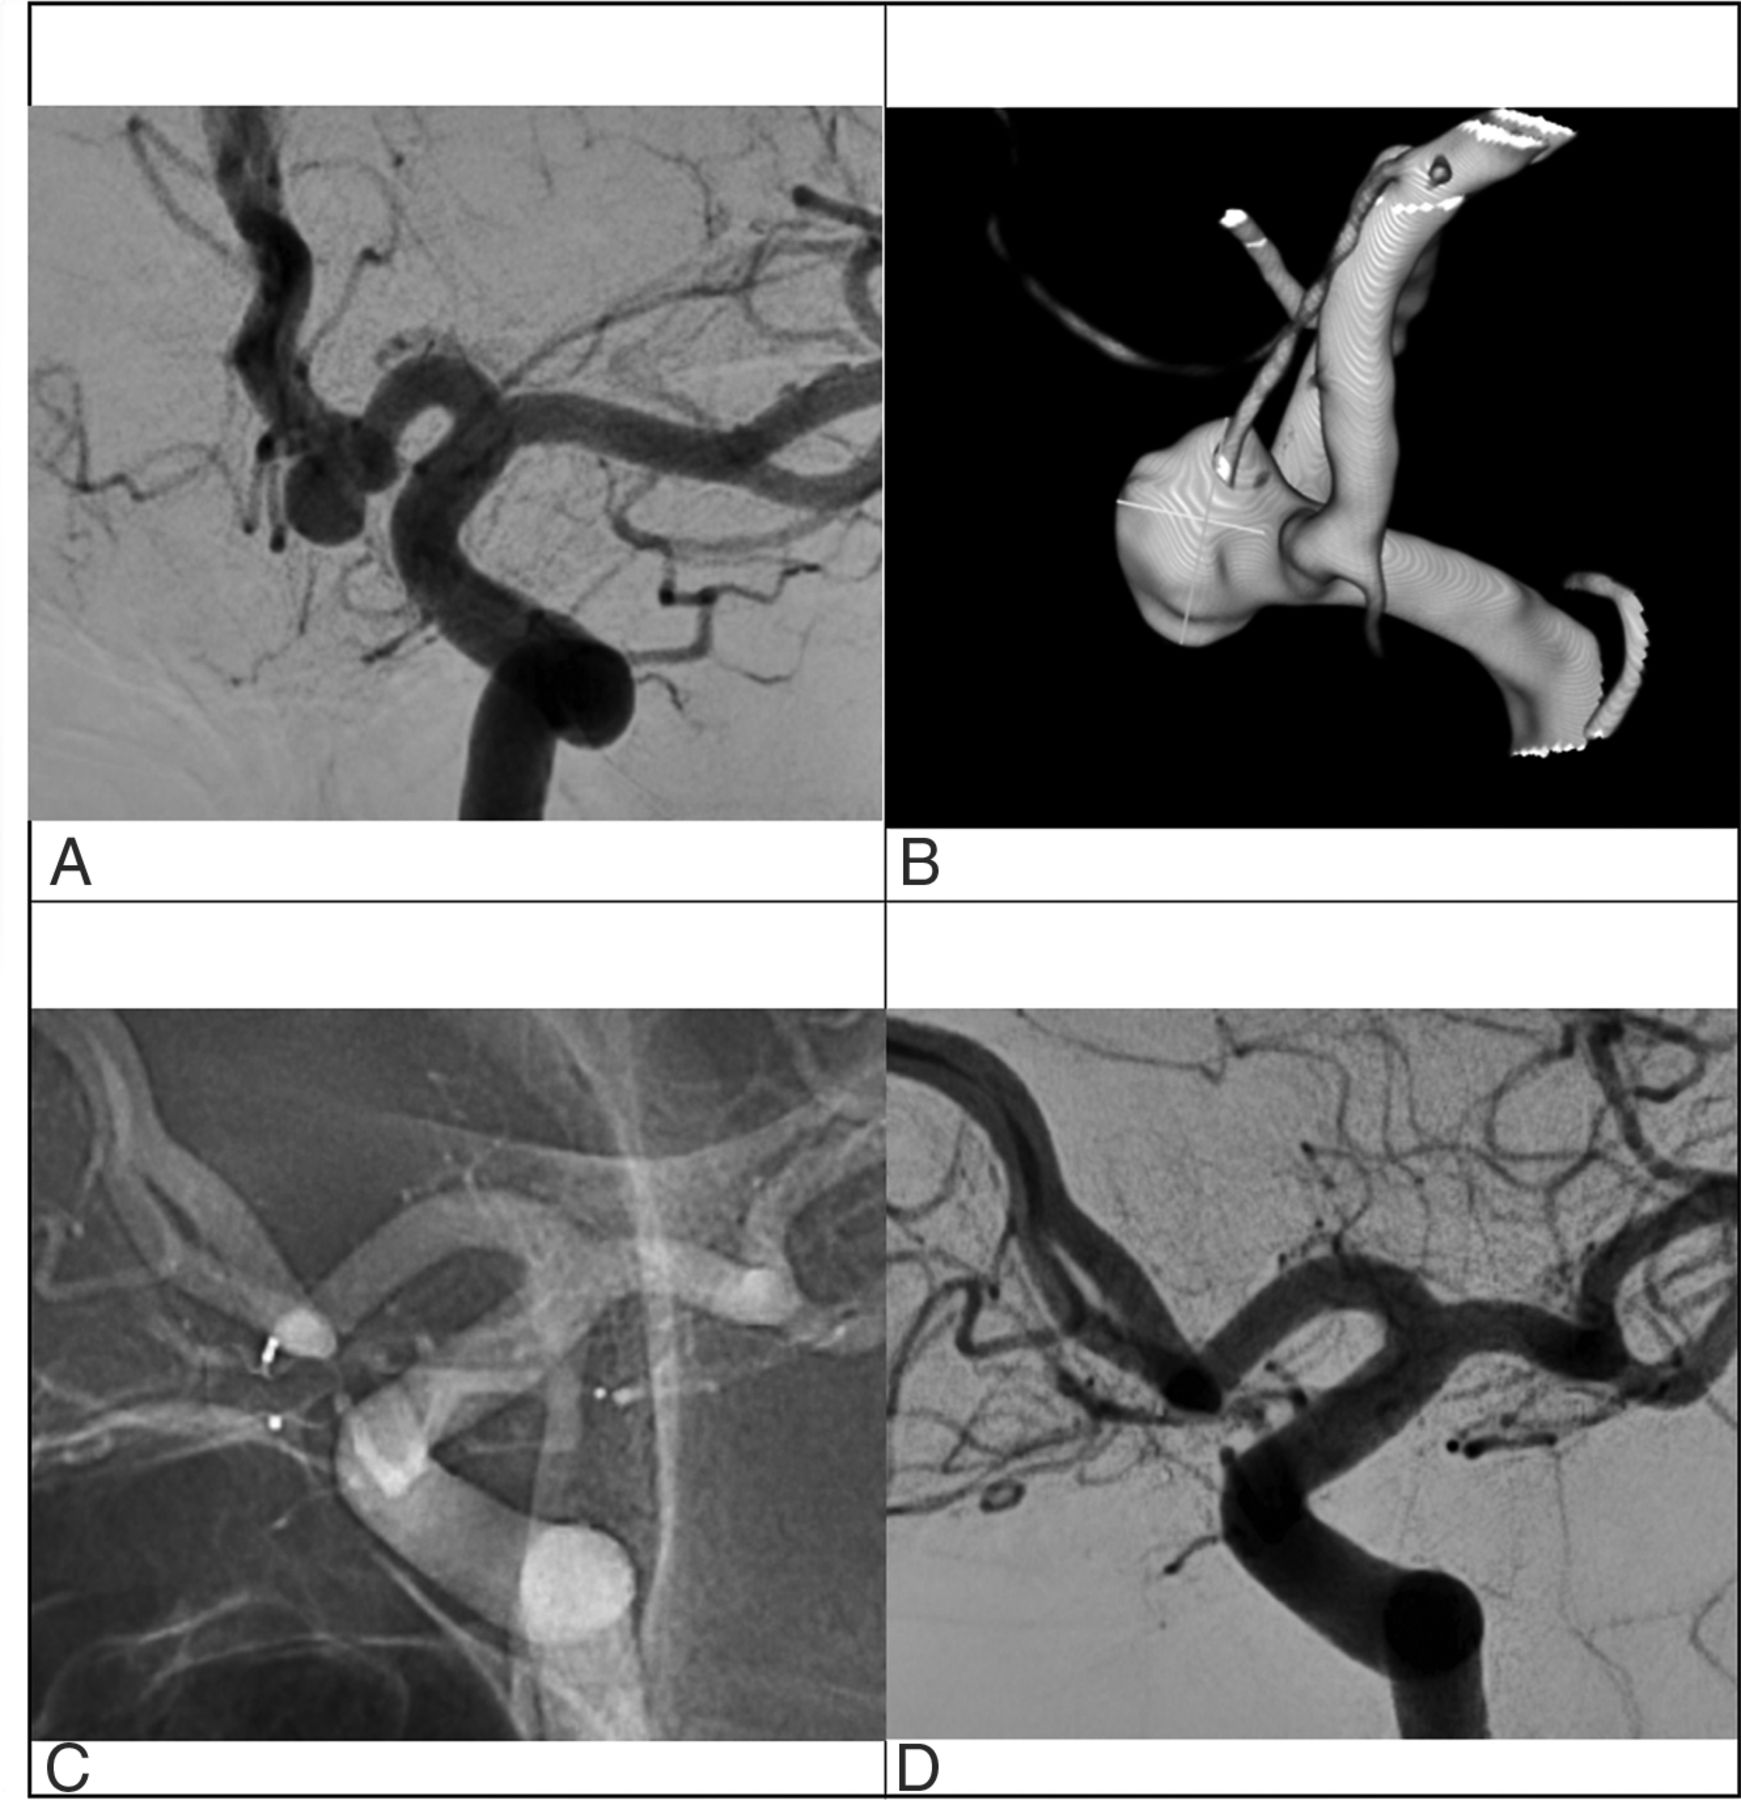

Our study of 48 ACoA aneurysms treated with the WEB device, in which we eliminated potential confounding factors using multivariate analysis, showed that unilateral A1 is a strong independent predictor of both adequate and complete occlusion (Fig 3, illustrative case). When an A1 segment was aplastic on 1 side (grade Y), leading to a unique unilateral blood flow entering the aneurysm, complete occlusion reached 93%. As intended by the sensitivity analysis, it seems that the definition of unilateral A1 could be extended to the absence of a functional A1 segment, which includes grade H3 in the definition.

Illustrative case of a ACoA aneurysm treated with a WEB device (A and B). The contralateral A1 segment is absent, rendering a Y-shape to the ACoA anatomy. Last control angiogram at 1-year follow-up demonstrates complete occlusion (C and D).